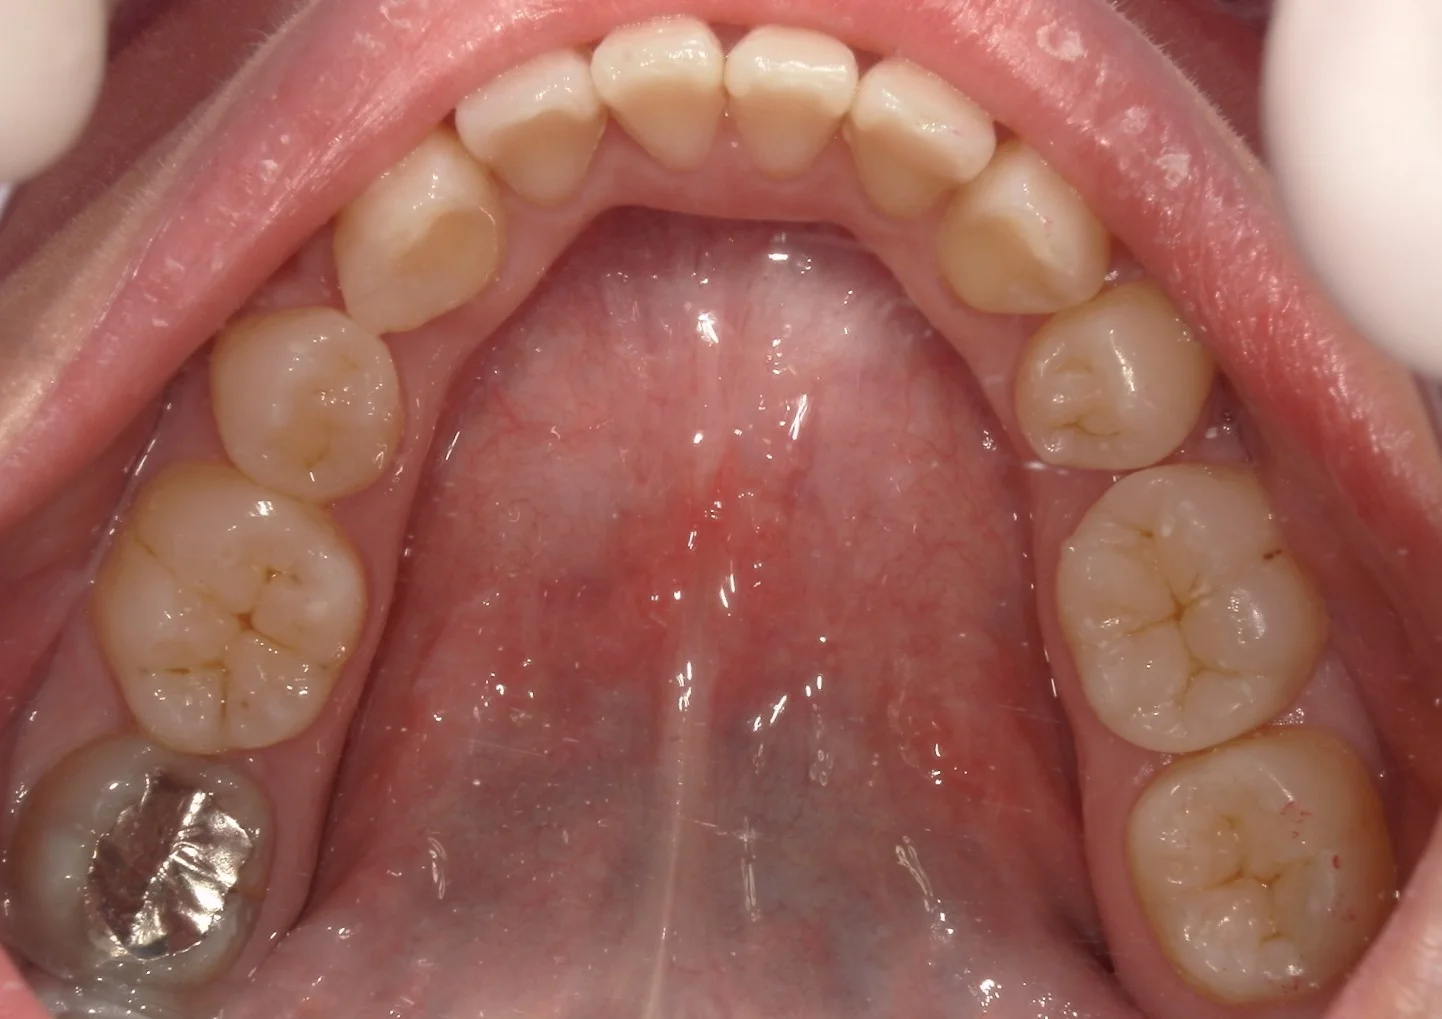

さて、この上下の歯のどこをどこを治療したでしょうか・・・!!

正解は下の方で・・・!

正解はこんな感じですヽ(゚∀゚)ノ パッ☆

計4回で治療終了まで行きました!